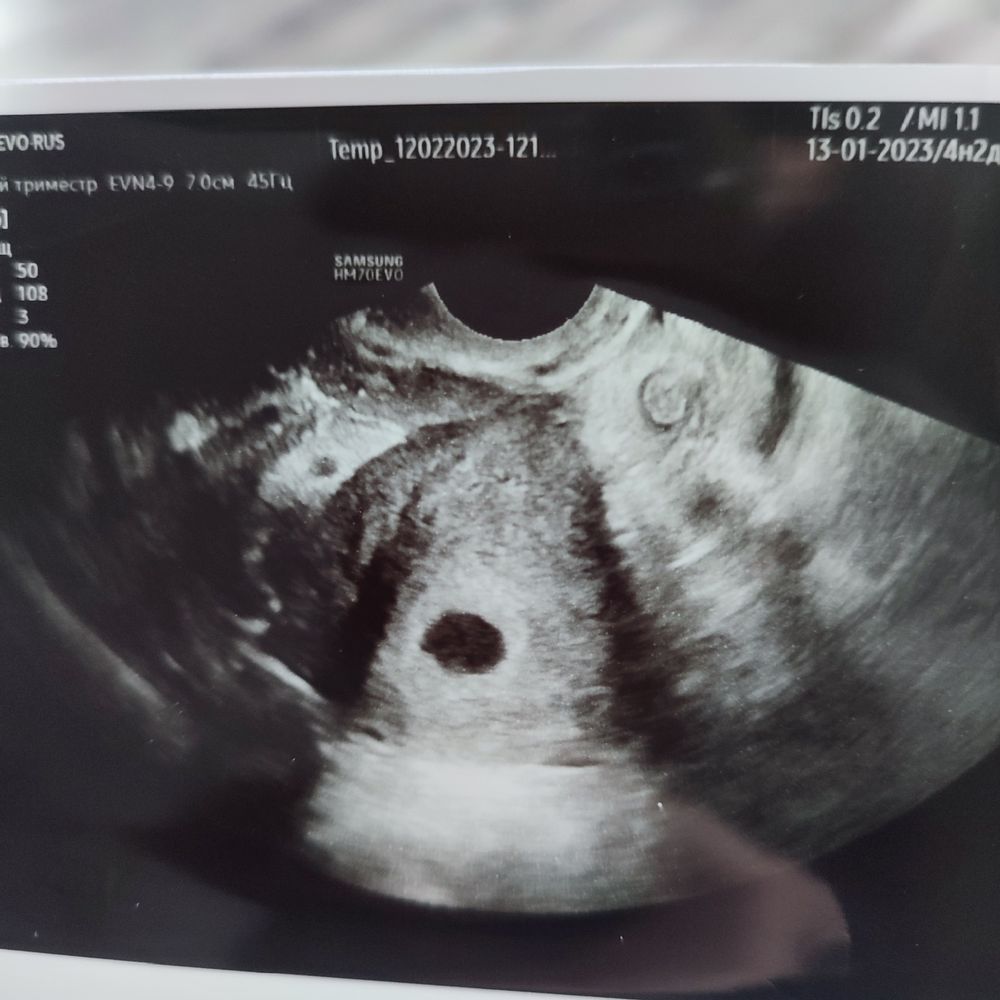

12.02 сделала первое УЗИ. Не удержалась ))) Акушерский срок 4 н.2 дня. Врач сказал, что по ПЯ срок не ставит (!), в заключении: 3-4 недели, "рост" 8 мм. Предложил придти 19.02, сказал что уже будет видно эмбрион... Стоит ли? Или лучше ещё подождать? Что то мозг меня совсем покинул 🙈🤣

У меня на первом УЗИ тоже пя 8 мм было и жм 1,6,через 9 дней повторно пя 19 мм,ктр 5,4 и ЧСС 146 уд/мин